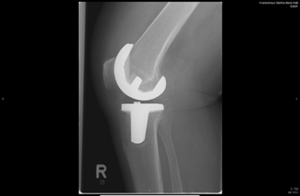

Röntgenbild eines Kniegelenkersatzes, sichtbar im rechten Kniebereich.

Mediale Schlittenprothese Knie in 2 Ebenen

Kompletter Oberflächenersatz/Totalendoprothese Knie in 2 Ebenen